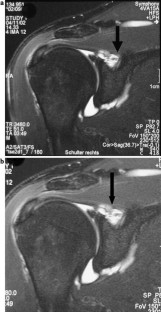

Fig. 1